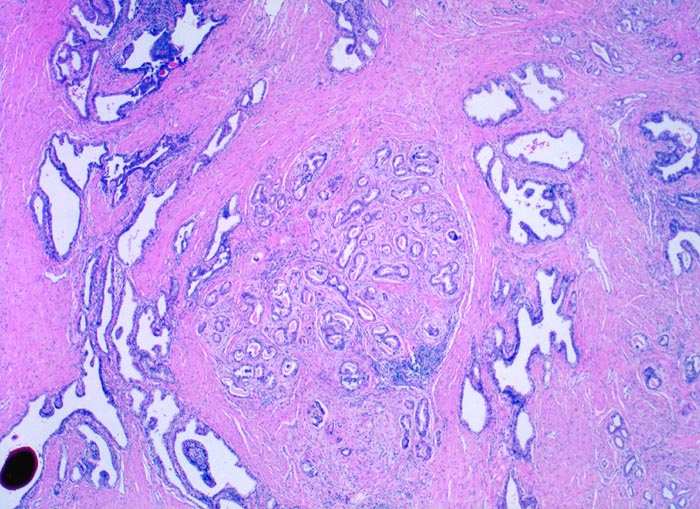

ETHZ spez/ Adenokarzinom der Prostata

Adenokarzinom der Prostata

Morphologische Merkmale:

• Normale Prostatadrüsen mit grossen Lumina angeordnet in Läppchen. Das Epithel bildet Falten und besteht aus einer inneren hochprismatischen sekretorischen Zellschicht und einer äusseren Schicht flacher Myoepithelien.

• Herde kleiner Karzinomdrüsen ohne Basalzellschicht.

• Fehlende lobuläre Anordnung der Karzinomdrüsen.

• Konfluierende Drüsen bilden kribriforme Muster.

• Karzinomzellen mit stark erhöhter Kern-Zytoplasmarelation und hyperchromatischen Zellkernen mit grossen eosinophilen Nukleolen.

• Wenig differenzierte Karzinomanteile ohne erkennbare Drüsenbildung.

• Perineuralscheideninvasion.

• Links oben im Präparat finden sich Anteile der Samenblase mit polymorphem Epithel und gelben Lipofuszinpigmenteinlagerungen.

• Unterhalb der Samenblase sind von flachem Endothel ausgekleidete Lymphgefässe mit Karzinominfiltraten erkennbar (Lymphangiosis carcinomatosa).

• Der mit schwarzer Tusche markierte Resektionsrand in der unteren Hälfte des Präparates ist tumorfrei.